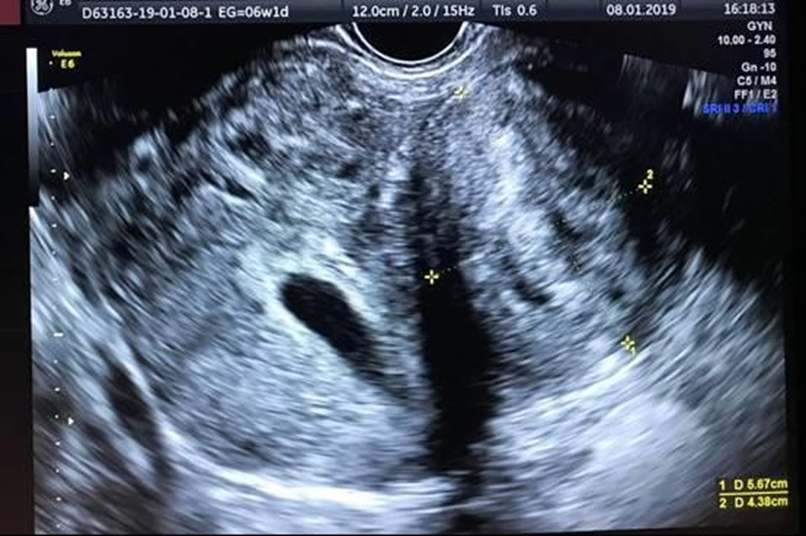

diet. At 39 weeks, caesarean was performed, obtaining a healthy female newborn with a birth weight of 2,930 Kg, Apgar score of 9 and 10 points and a cord pH of 7.31. Mother and daughter are discharged on the third day of surgery without complications. Mother Breastfed for 9 months and at 3 months post-cesarean section, a transvaginal ultrasound was performed, showing a notable reduction in the size of the fibroids (no myoma observed in anterior uterus surface):

A) Posterior myoma measuring 24 x 20 mm, type V FIGO classification

B) Fundic fibroid measuring 28 x 21 mm, type VI FIGO classification

C) Left transmural myoma measuring 35 x 25 mm, type IV FIGO classification (Figure 3).

Figure 3. Left transmural myoma in pregnancy diagnosis moment.